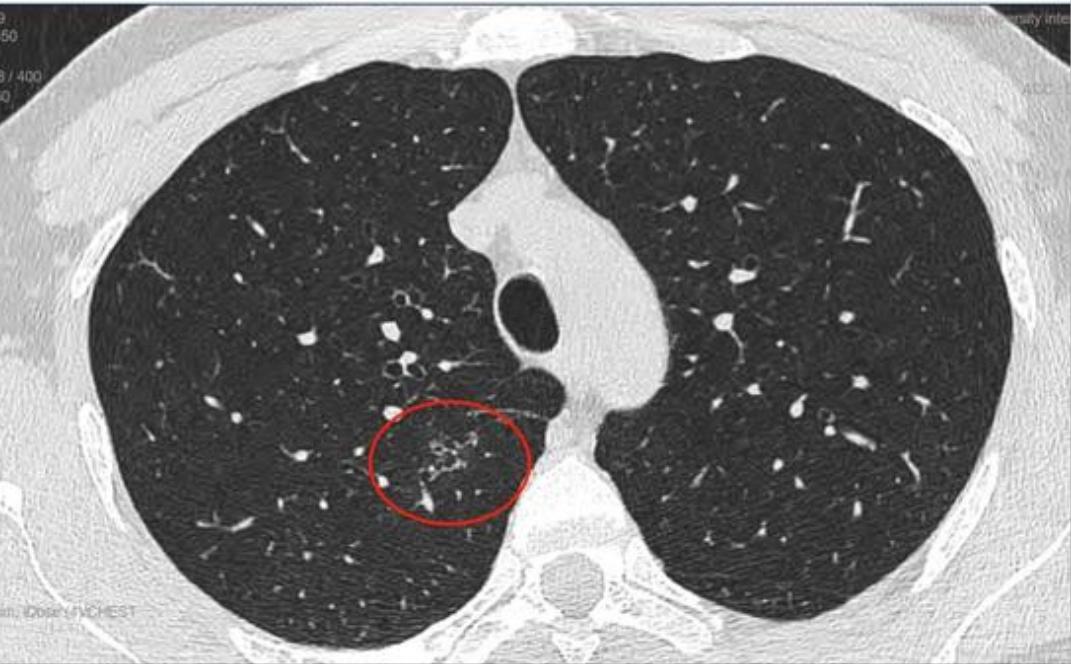

这是11月15日的CT图像与上次(7月29日)CT图像对比图:

再发一张:

辛苦主任,您看一下,结节虽然缩小了,还有1.7*0.9 CM,其他俩肺叶还有陈旧性病灶,应该继续服用拜复乐和夏枯草吗?8月份查过:男性肿标9项、过敏源检测(总IgE)、鳞状上皮细胞癌相关抗原、GM试验、隐球菌抗原、1,3-β-D葡聚糖 都是阴性,在正常范围内。就是结核感染T细胞还没查,您看是否需要查一下?主任辛苦您了,谢谢您!

敬爱的戴主任,有个好消息跟您汇报,我老公的肺结节听您的建议服用拜复乐和夏枯草后缩小啦,7月29日的CT报告是1.9*1.1cm,同一家医院11月15日的CT报告是1.7*0.9cm,颜色也变浅了,您真是火眼金睛,华佗在世,我们的保护神!我们全家人的恩人!真心地谢谢您!